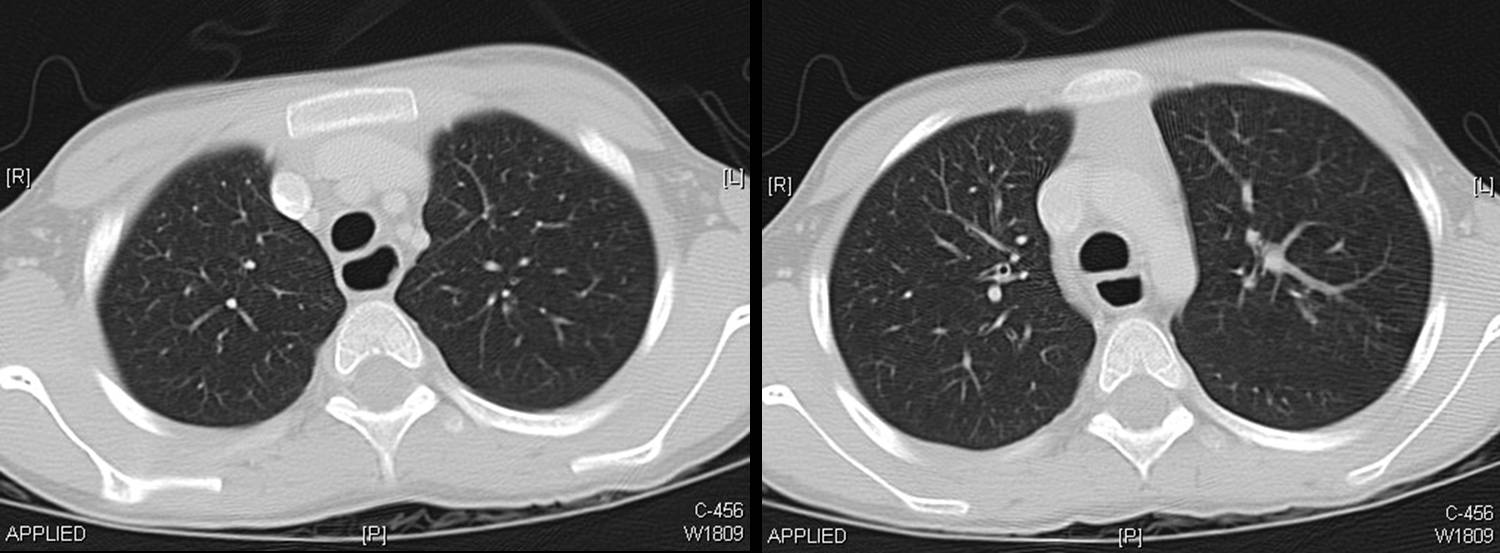

A CT scan of chest was done.

The following screen shows the images from the Chest CT.

| Figure 4-a | Figure 4-b | Figure 4-c |

| Figure 4-d | Figure 4-e | Figure 4-f |

| Figure 4-g |